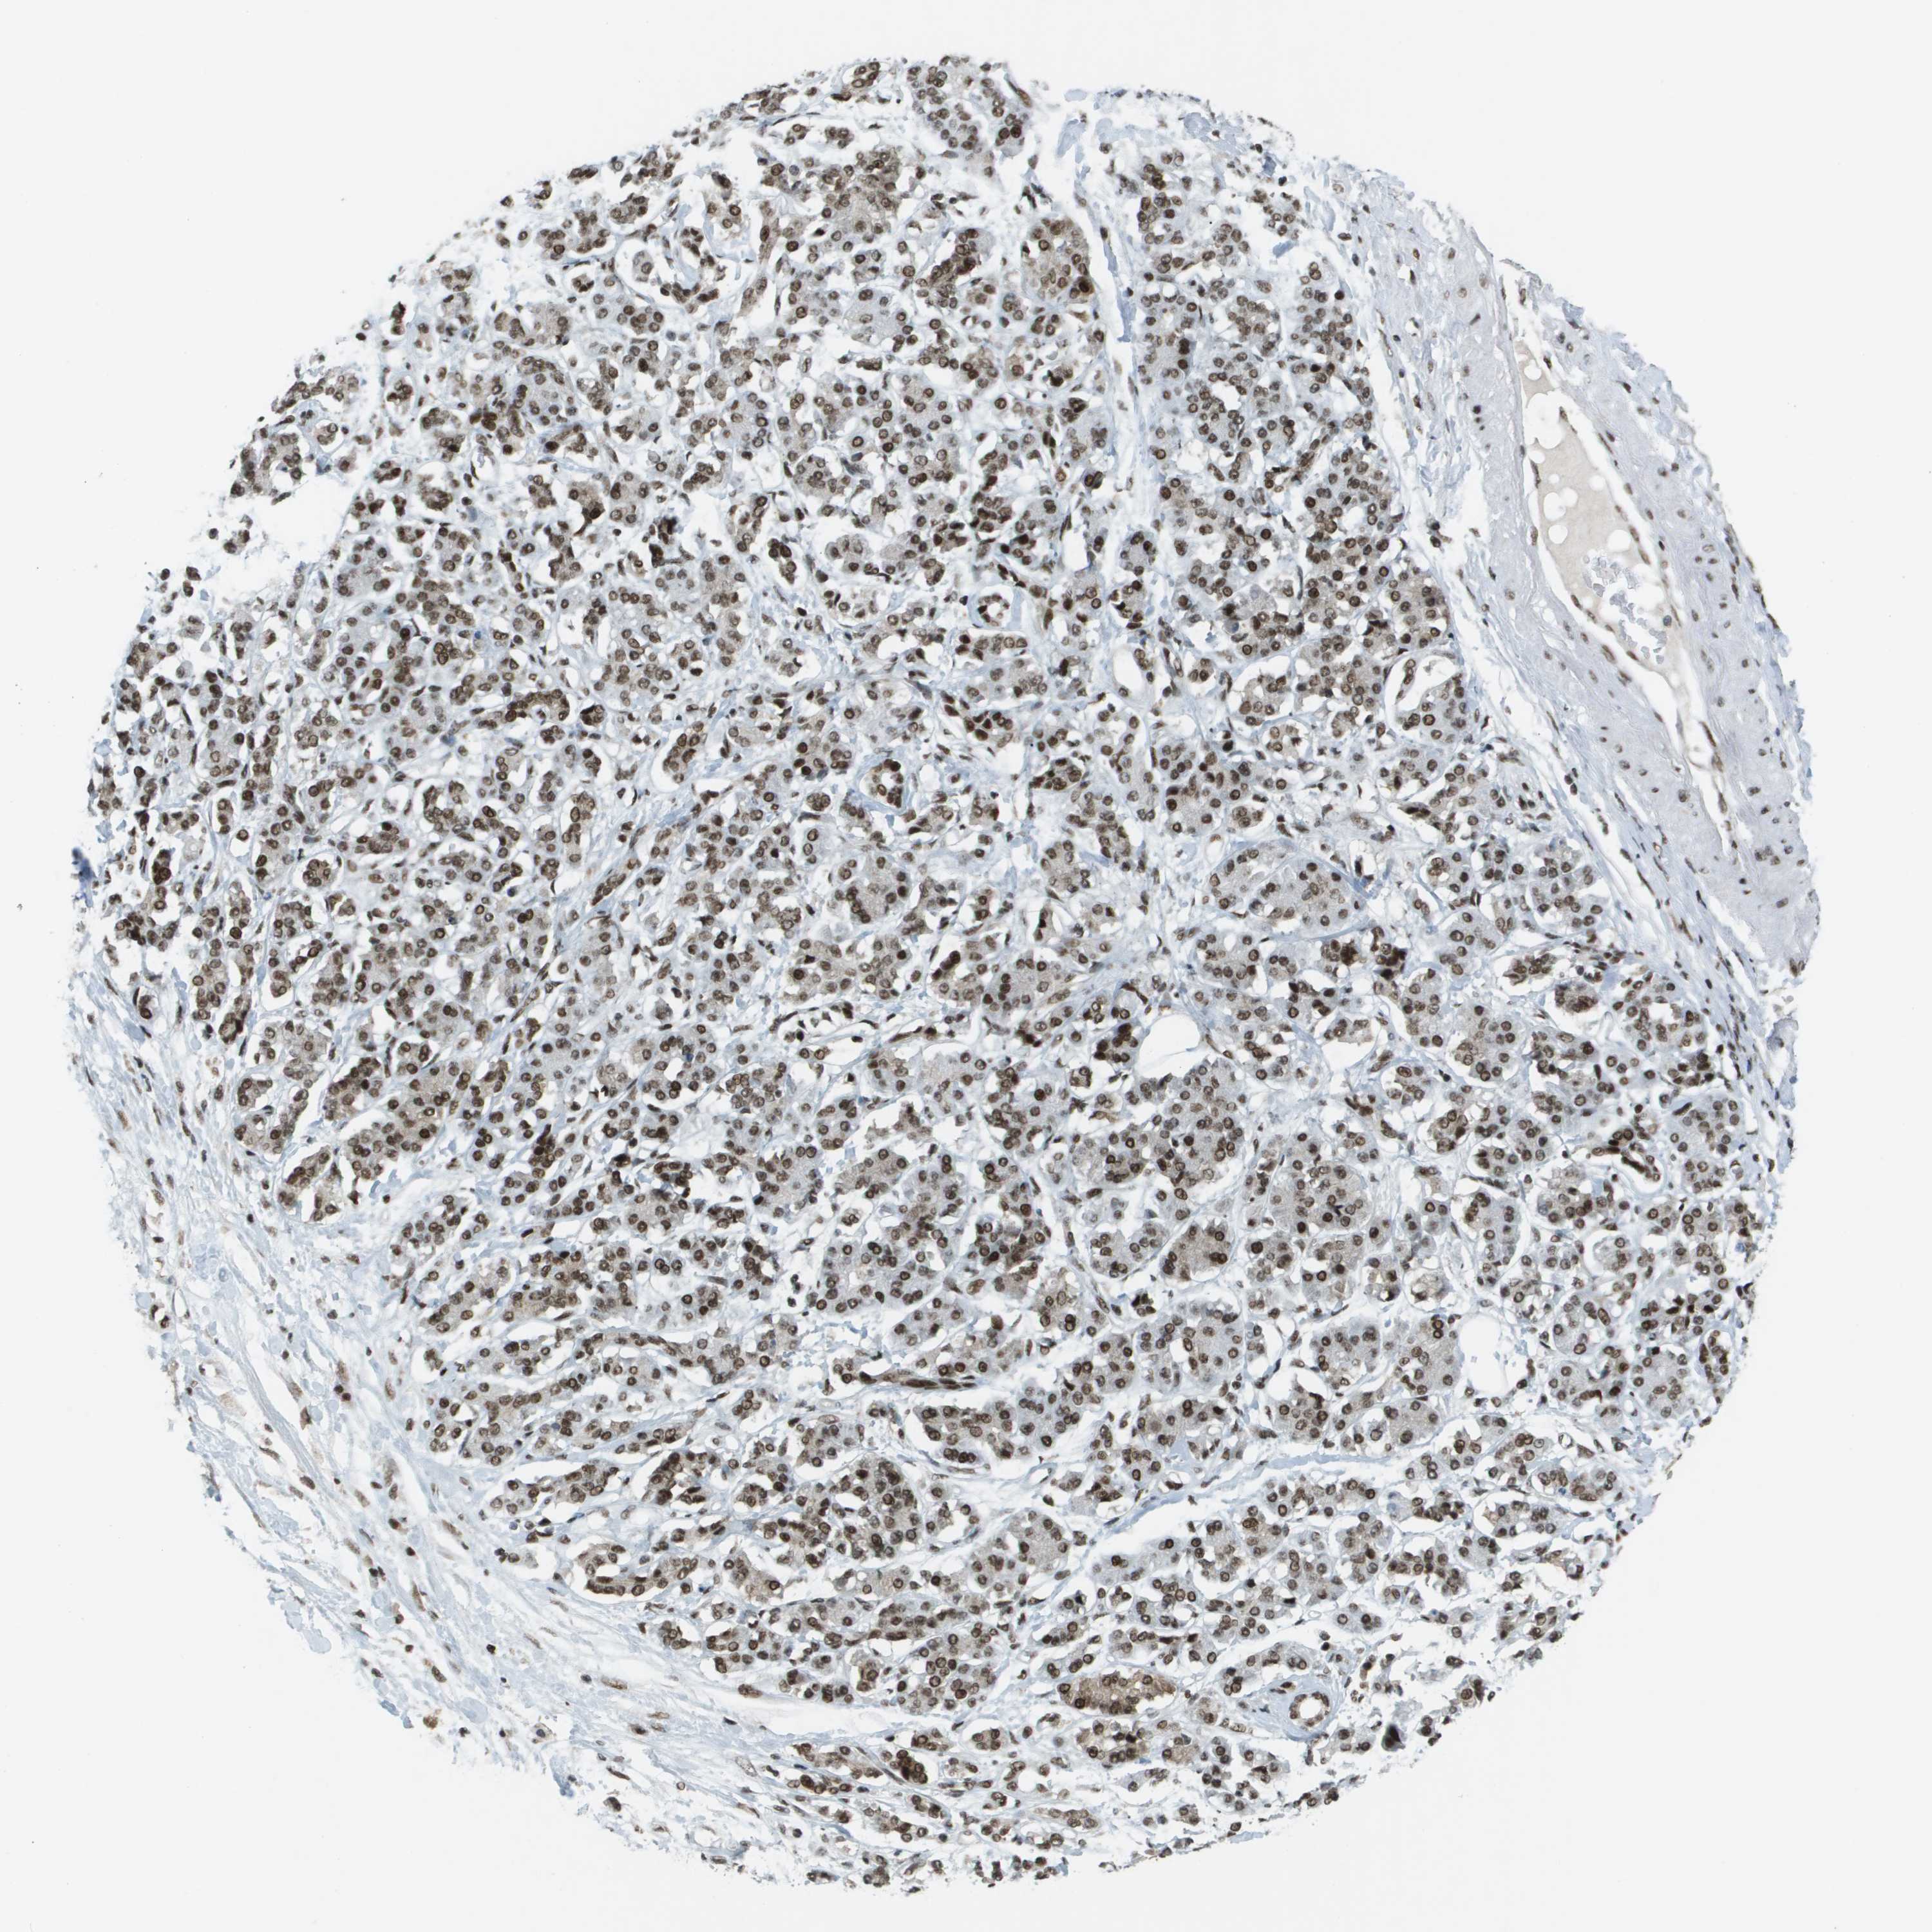

PANCREATIC CANCER - Protein expressioni

A mouse-over function shows sample information and annotation data. Click on an image to view it in a full screen mode. Samples can be filtered based on level of antibody staining by selecting one or several of the following categories: high, medium, low and not detected. The assay and annotation is described here.

Note that samples used for immunohistochemistry by the Human Protein Atlas do not correspond to samples in the TCGA dataset.

Antibody stainingi

Antibody staining in the annotated cell types in the current human tissue is reported as not detected, low, medium, or high, based on conventional immunohistochemistry profiling in selected tissues. This score is based on the combination of the staining intensity and fraction of stained cells.

Each image is clickable and will lead to virtual microscopy that enables deeper exploration of all samples and also displays staining intensity scores, fraction scores and subcellular localization as well as patient and tissue information for each sample.

Antibody HPA052757

Antibody CAB017694

Staining

High

Medium

Low

Not detected

Intensity

Strong

Moderate

Weak

Negative

Quantity

>75%

75%-25%

<25%

None

Location

Nuclear

Cytoplasmic/membranous

Cytoplasmic/membranous,nuclear

Adenocarcinoma, NOS